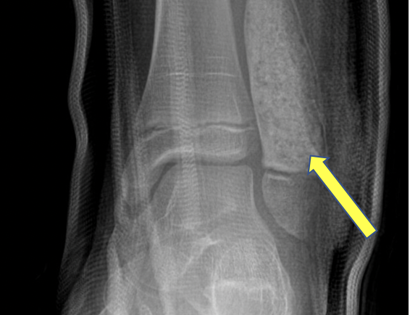

Radiographic imaging is used to help form a diagnosis of ABC. These include X-Ray, MRI, CT and Bone Scans.

An example of an ABC X-Ray (Figure 1A) and an MRI (Figure 1B) with fluid fluid levels are shown.